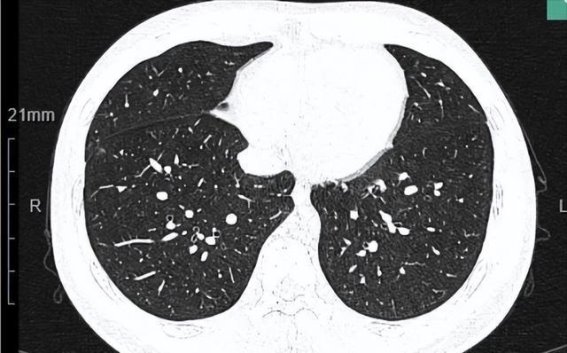

磨玻璃结节在如今的医学检查中并不罕见,尤其是在肺部CT扫描中,这种结节往往会引起患者的高度关注和担忧。大多数情况下,磨玻璃结节并不像它的名字那样具有明确的威胁性。···